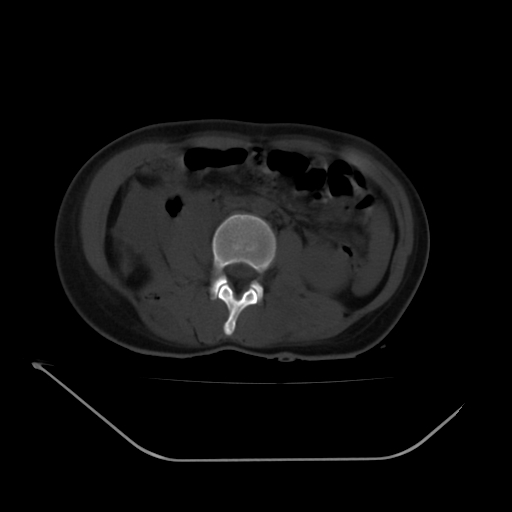

以下是引用liuyue在2008-7-19 13:02:00的发言:[br]1.肝右叶后下段及右肾挫裂伤伴腹腔积血。[br]2.右侧多发性肋骨骨折、横突骨折、右髂骨骨折伴周围软组织挫伤。[br]3.右侧腰大肌肿胀,并可见低密度影,如为气体,则肠道挫裂伤待除外。

以下是引用zhengfaming在2008-7-19 14:42:00的发言:[br]1.肝右叶后下段及右肾挫裂伤伴腹腔积血。脾脏挫裂伤待排[br]2.右侧多发性肋骨骨折、横突骨折、右髂骨骨折伴周围软组织挫伤。[br]3.右侧腰大肌肿胀,并可见低密度影,如为气体,则肠道挫裂伤待除外